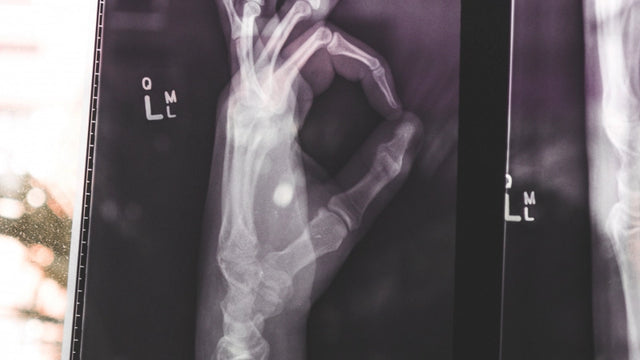

Görüntü teşhisi, doktorların tıbbi durum hakkında şüpheler bulmak için vücudun iç kısmını gözlemlemelerini kabul eder ve nükleer tıp, hastalıkların teşhisi ve tedavisi için kullanılır. Bu nedenle, bu ders ile nükleer tıbbın tanı ve özellikleri için görüntü tekniklerini bilmek için gerekli bilgileri sağlamak amaçlanmaktadır.

- Teşhis görüntüsünün farklı yöntemlerini açıklayın. - Radyografik tekniğin farklı ilkelerini öğrenin. - Nükleer tıbbın görüntü tekniklerinin temel yönlerini bilin.

Teşhis ve nükleer tıp için bu görüntü teknikleri, vücudun içindeki olası koşulları aramak için görüntüler aracılığıyla farklı teknikleri bilmeye hazırlar.